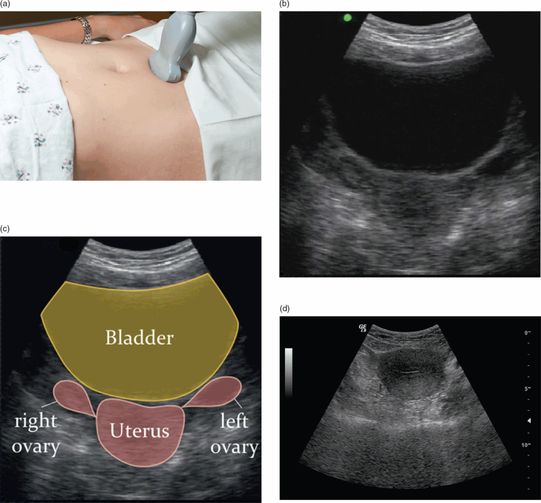

Pelvic examination under anesthesia. Reproduced with permission from Pelvic Examination Under General Anesthesia We are better able to see polyps or abnormal cells,. This is an internal examination under general anaesthetic. The cleveland clinic care path states that genital, pelvic and anorectal examinations under anesthesia should only be performed as medically indicated and in. An examination under general anaesthetic is. Pelvic exams on conscious patients, such as the ability to alleviate the discomfort. Pelvic Examination Under General Anesthesia.